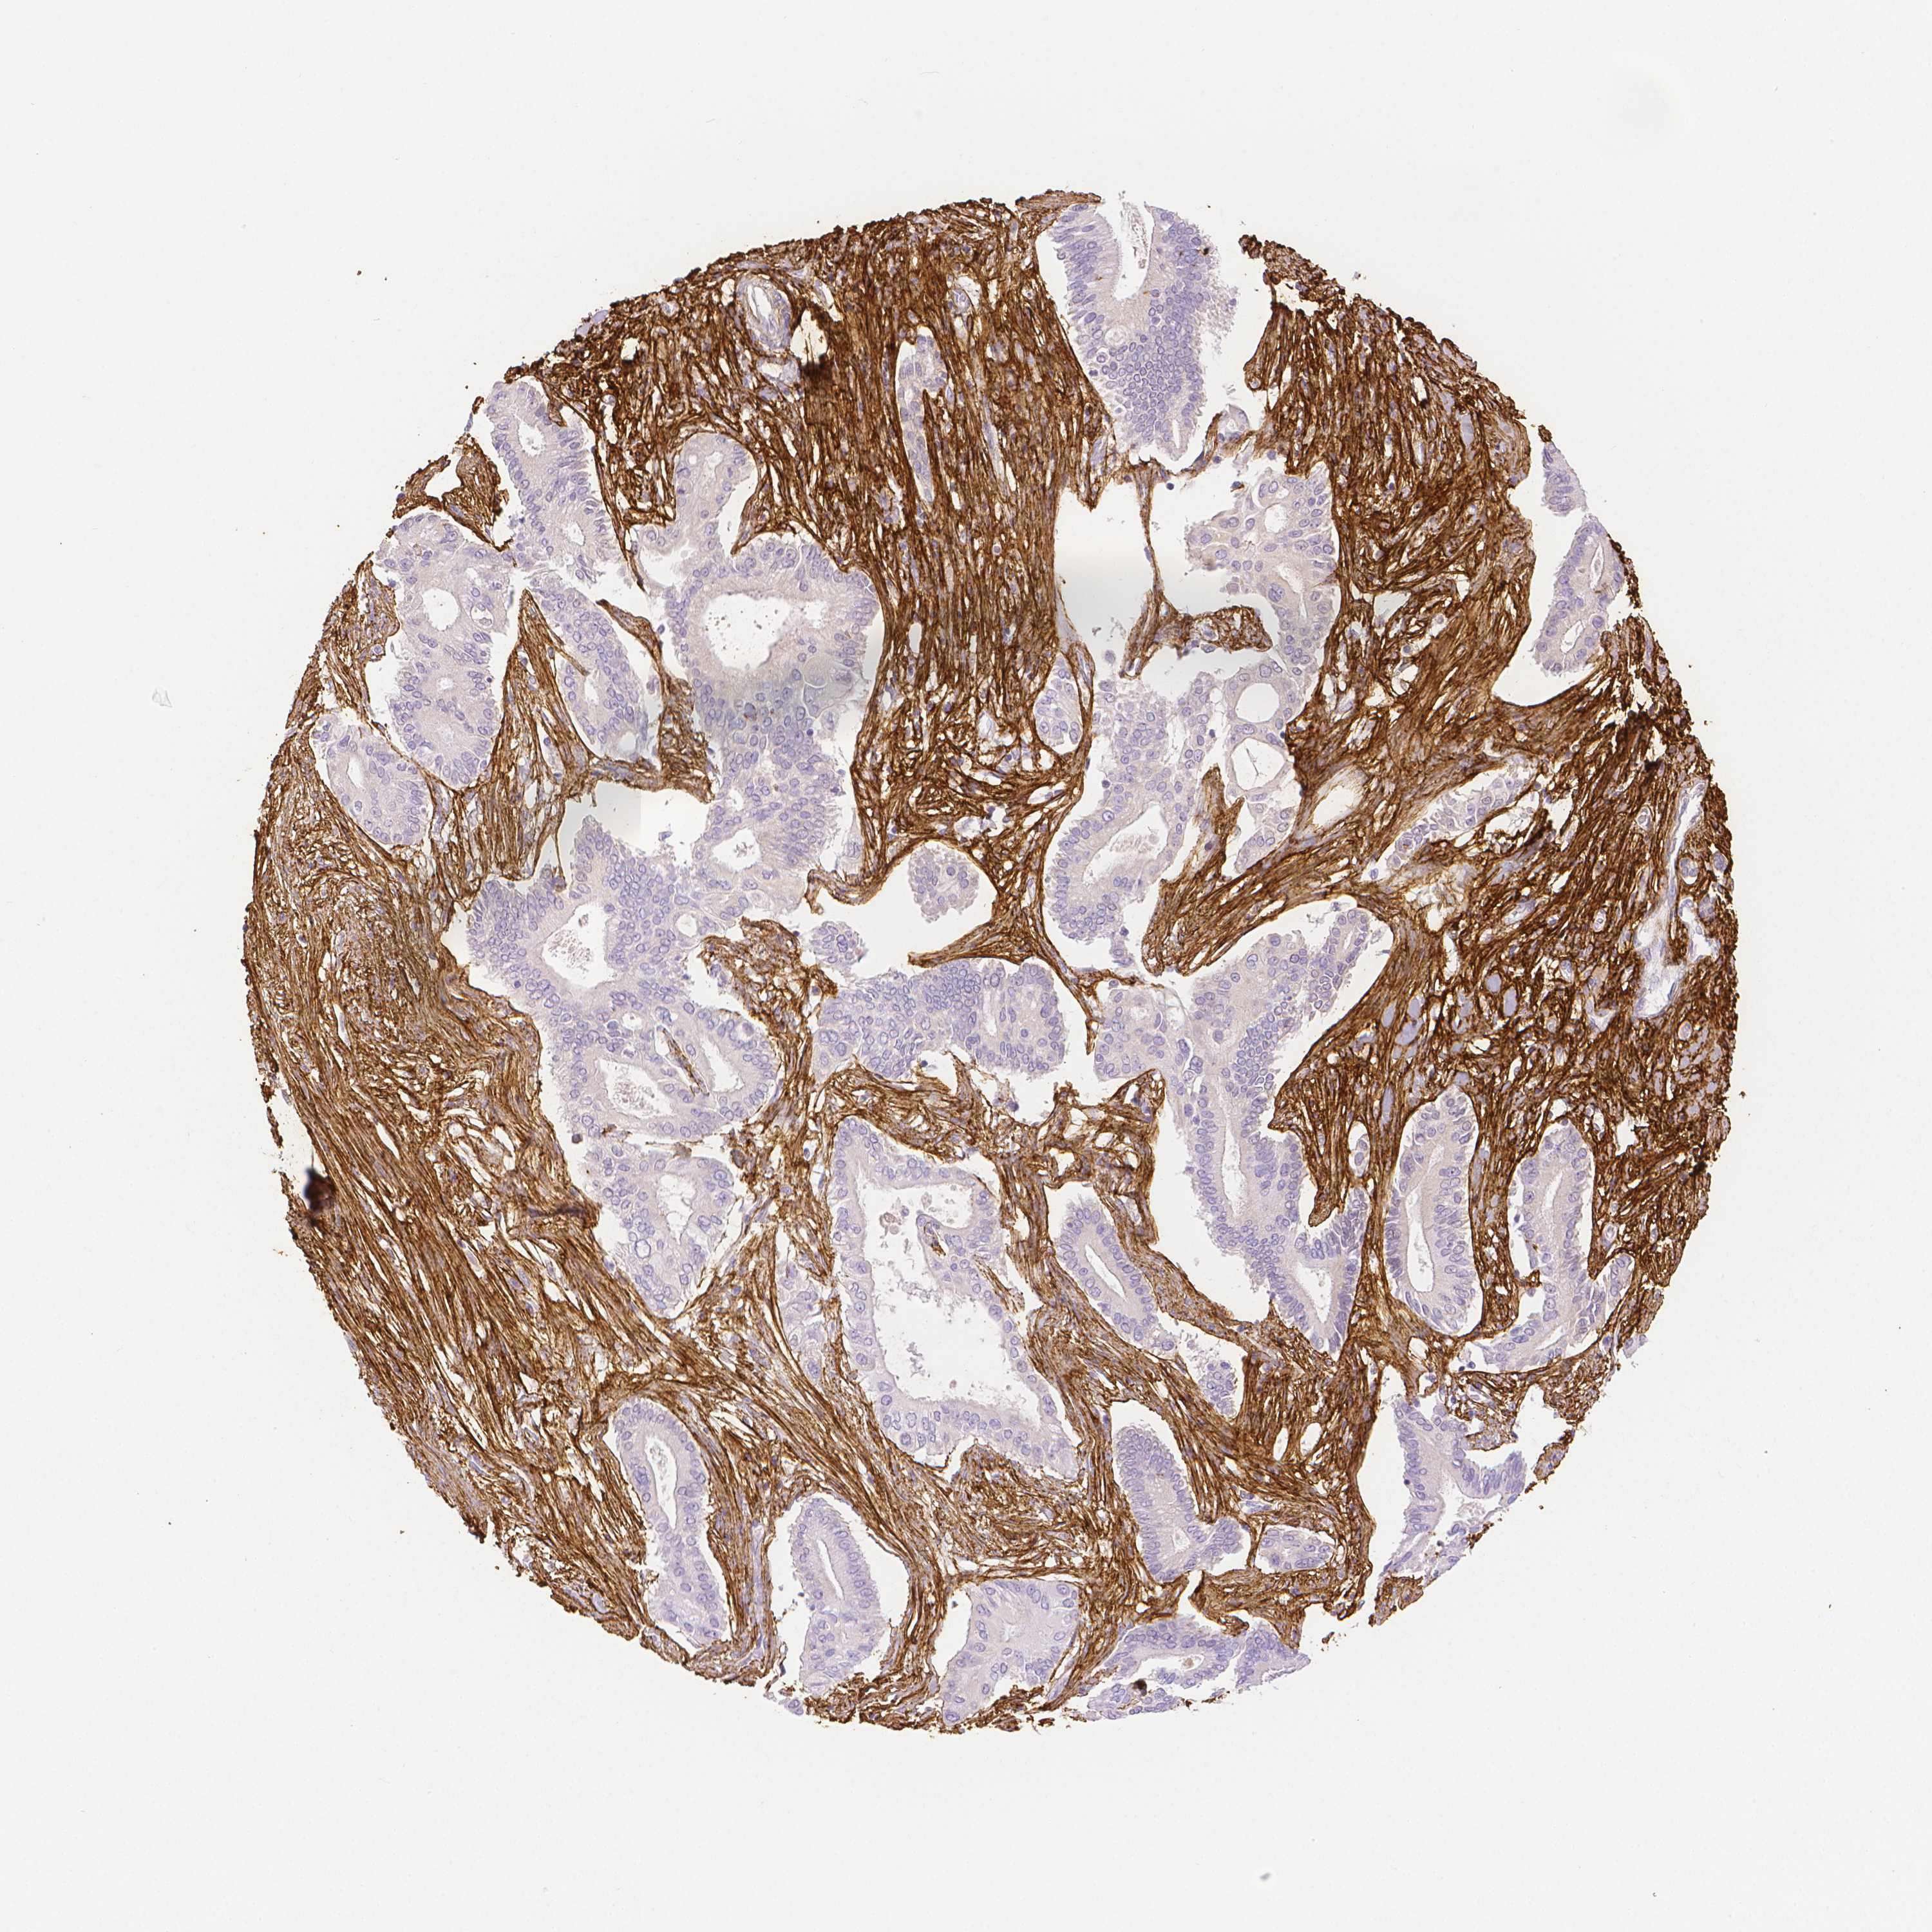

PANCREATIC CANCER - Protein expressioni

A mouse-over function shows sample information and annotation data. Click on an image to view it in a full screen mode. Samples can be filtered based on level of antibody staining by selecting one or several of the following categories: high, medium, low and not detected. The assay and annotation is described here.

Note that samples used for immunohistochemistry by the Human Protein Atlas do not correspond to samples in the TCGA dataset.

Antibody stainingi

Antibody staining in the annotated cell types in the current human tissue is reported as not detected, low, medium, or high, based on conventional immunohistochemistry profiling in selected tissues. This score is based on the combination of the staining intensity and fraction of stained cells.

Each image is clickable and will lead to virtual microscopy that enables deeper exploration of all samples and also displays staining intensity scores, fraction scores and subcellular localization as well as patient and tissue information for each sample.

HPA017759

HPA021057

CAB002670

CAB058696

CAB068188

CAB080202

Staining

High

Medium

Low

Not detected

Intensity

Strong

Moderate

Weak

Negative

Quantity

>75%

75%-25%

<25%

None

Location

Nuclear

Cytoplasmic/membranous

Cytoplasmic/membranous,nuclear

Adenocarcinoma, NOS

Adenocarcinoma, metastatic, NOS